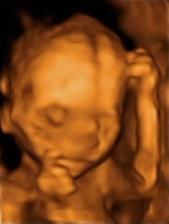

Už víme z 3D ultrazvuku, že čekáme další holčičku. Jméno máme zatím jen ,,pracovní,,...Jasmínka. Ještě nemáme s manželem jasno. Chtěli bysme totiž něco krátkého, když příjmením bude Kovářová. Termín porodu mám 16. července 2010. Bude to určitě náročné miminko a ten náš čertík, ale i tak se na miminko moc těším.